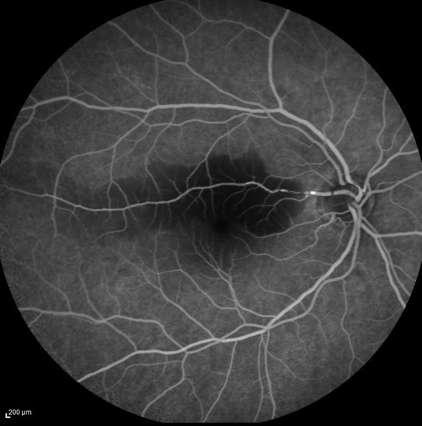

Imágenes aportadas por Dr. Cristian Sánchez

ü La degeneración macular relacionada a la edad es la causa más frecuente de pérdida de visión irreversible en personas mayores de 60 años

ü La patogenia es multifactorial, en que además del envejecimiento (principal factor de riesgo) los factores de riesgo genéticos y ambientales (Tabaquismo, obesidad abdominal) juegan un rol determinante

ü Su primera manifestación son las drusas sin embargo el proceso puede evolucionar a la forma seca o húmeda

ü La forma húmeda se caracteriza por la presencia de membrana neovascular coroidea que crece bajo el epitelio pigmentario y luego bajo la retina. Estos vasos de neoformación se originan en la coriocapilar, proliferan y penetran al espacio subepitelial a través de una ruptura de la membrana de Bruch

ü El desprendimiento de epitelio pigmentario puede preceder la neovascularización coroidea, y en ese caso su contenido es seroso, cuando se asocia a neovascularización coroidea su contenido es fibrovascular

ü Al examen oftalmoscópico, en caso de tener una membrana neovascular, se detecta un solevantamiento retinal, habitualmente redondeado y generalmente rodeado de un halo de sangre subretinal. El solevantamiento se debe a la presencia de líquido o edema retinal. La membrana neovascular puede ser extrafoveal, alejada del centro, pero en la mayoría de los casos es subfoveal

ü Una complicación inusual es la hemorragia subretinal masiva, lo que en algunos pacientes se asocia a terapia anticoagulante

ü Angiografía con fluoresceína en la membrana MNVC Tipo Ia (DEP fibrovascular): se caracteriza por presentar área hiperfluorescente irregular visible desde un tiempo arteriovenoso precoz que incrementa la fluoresceina en tiempos tardíos con poca o nula difusión

2.G. MEMBRANA NEOVASCULAR COROIDEA (MNVC)

Clement F . “Angiografía”. Diagnóstico por la imagen en la retina, Sociedad Española de Retina y Vítreo, editado por Ignasi Jügens, Elservier, 2014, pp 41-66 Juan Verdaguer, T. (2010). Degeneración macular relacionada a la edad. Revista Médica Clínica Las Condes, 21(6), 949–955. doi:10.1016/s0716-8640(10)70620-9

A B